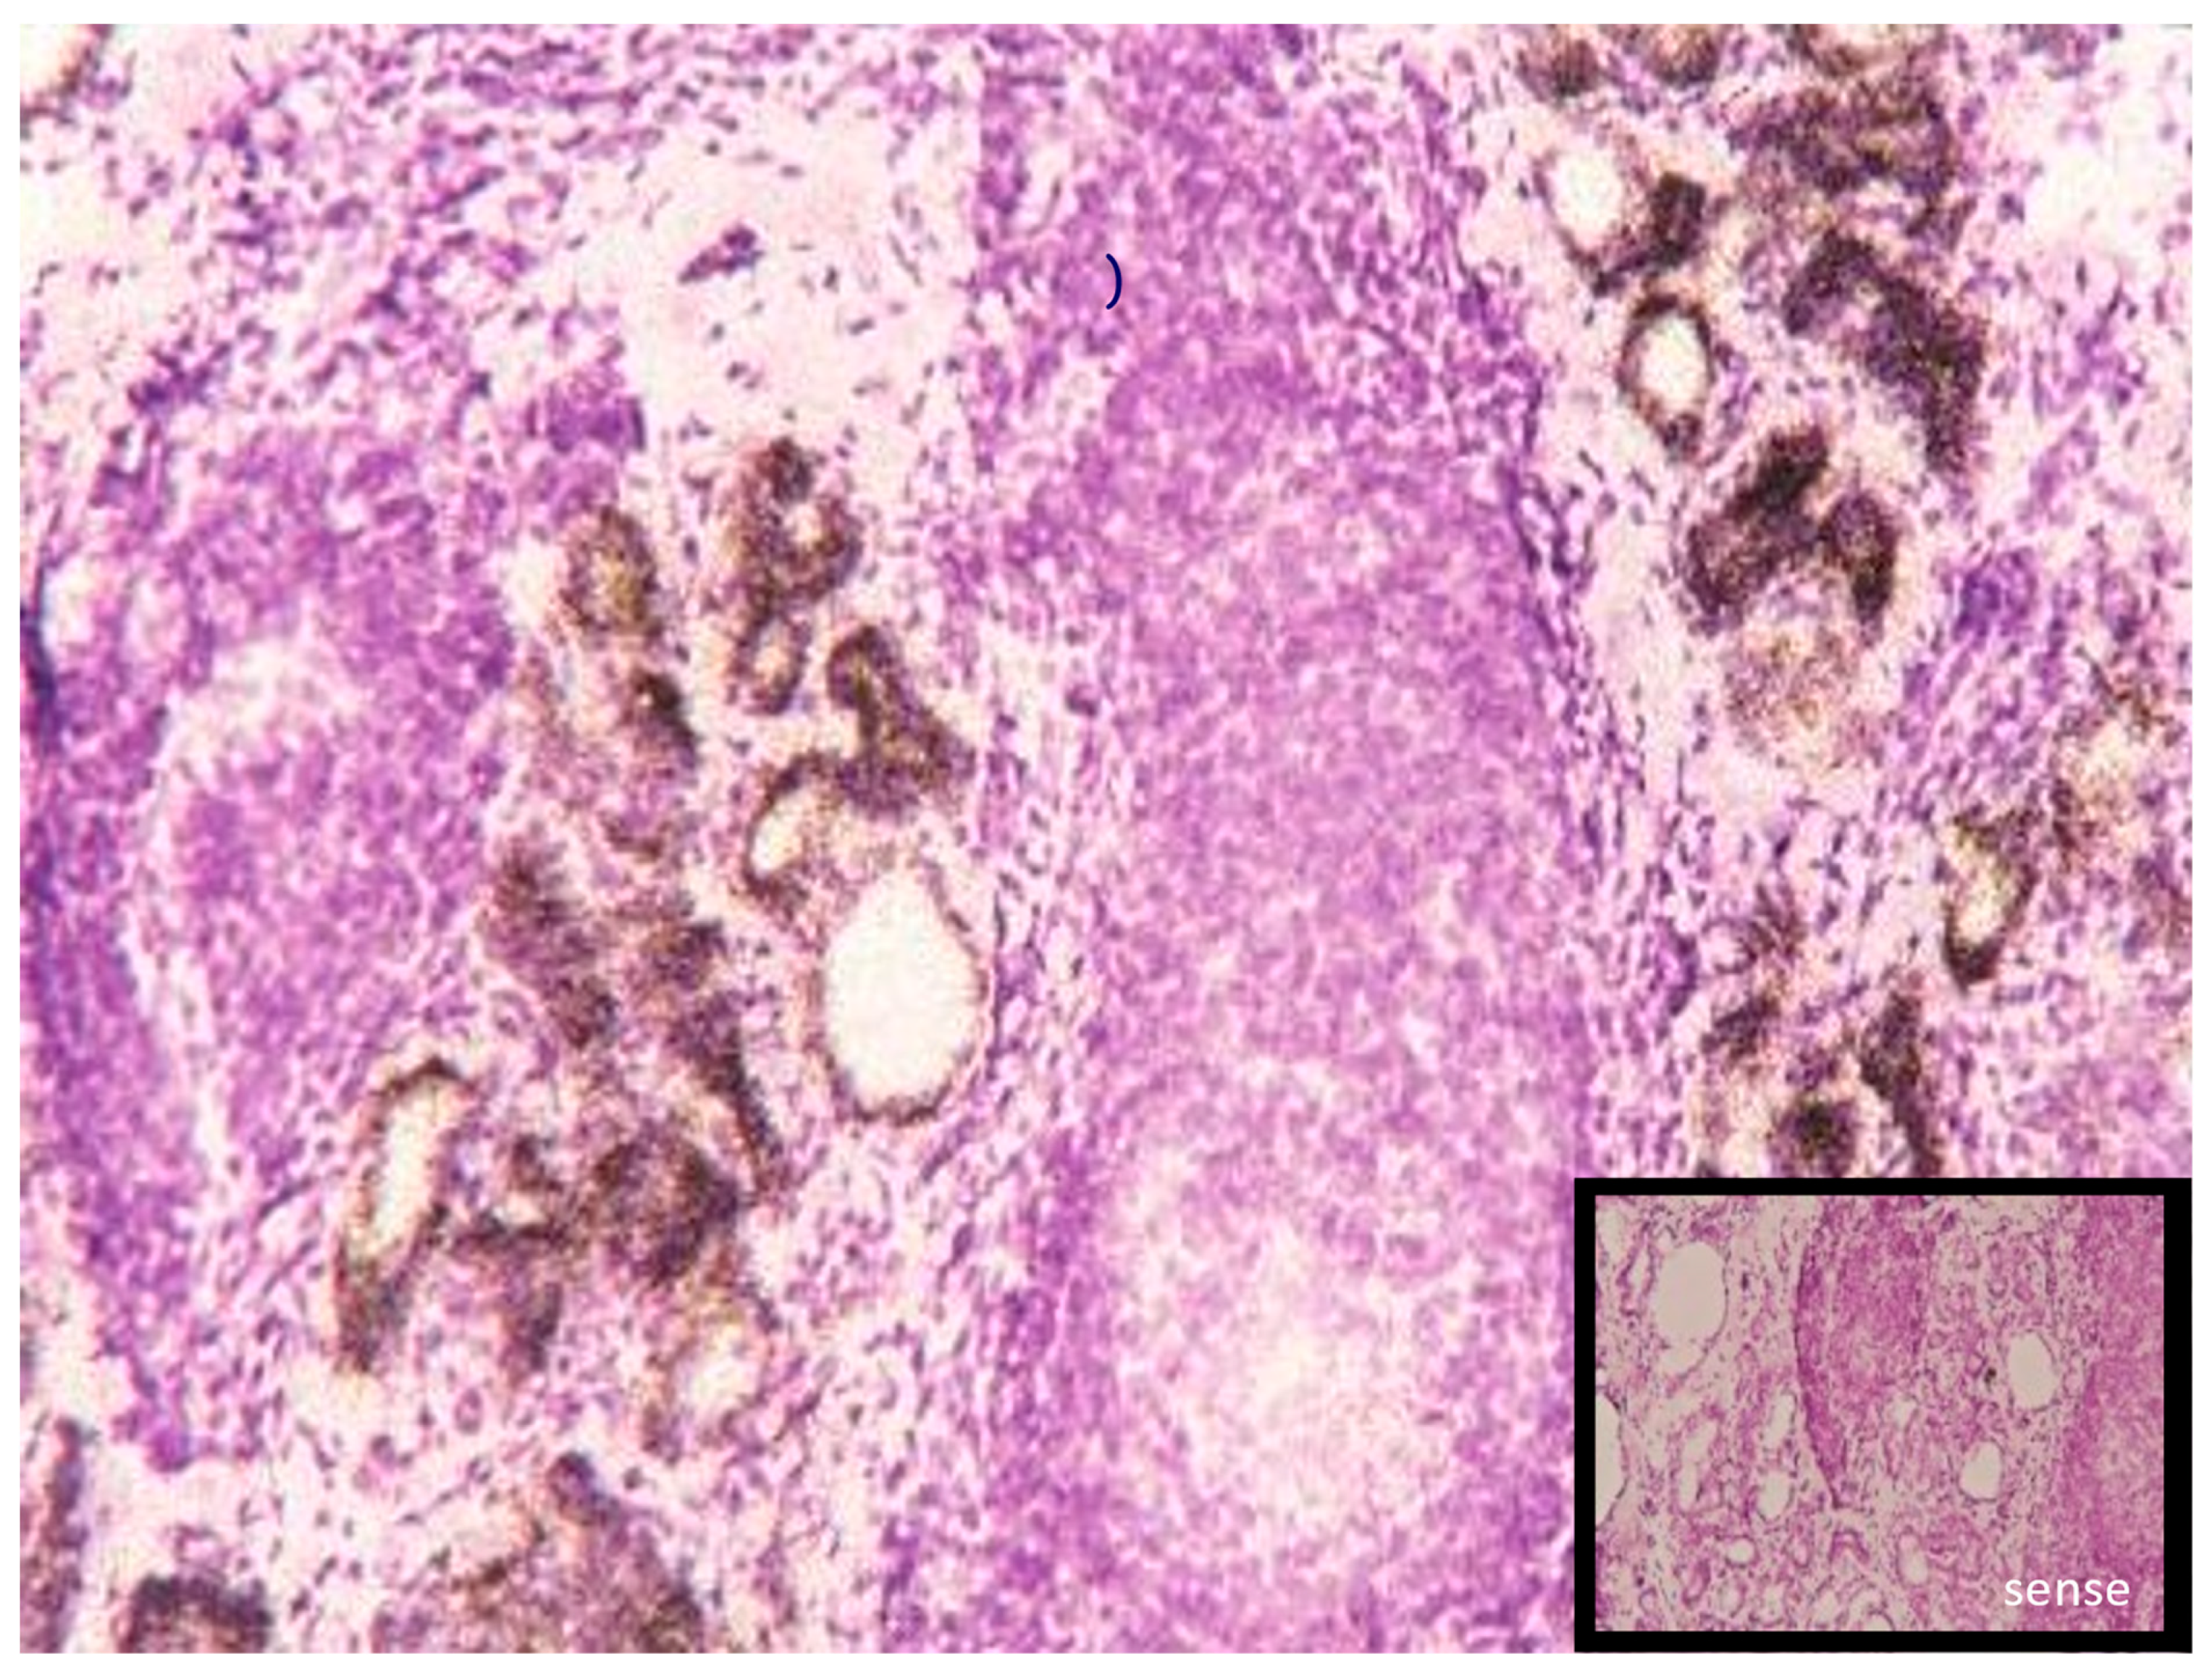

- Contempre, B.; Le Moine, O.; Dumont, J.E.; Denef, J.F.; Many, M.C. Selenium deficiency and thyroid fibrosis. A key role for macrophages and transforming growth factor beta (TGF-beta). Mol. Cell. Endocrinol. 1996, 124, 7–15. [Google Scholar] [CrossRef] [PubMed]

- Contempre, B.; Dumont, J.E.; Denef, J.F.; Many, M.C. Effects of selenium deficiency on thyroid necrosis, fibrosis and proliferation: A possible role in myxoedematous cretinism. Eur. J. Endocrinol. 1995, 133, 99–109. [Google Scholar] [CrossRef] [PubMed]